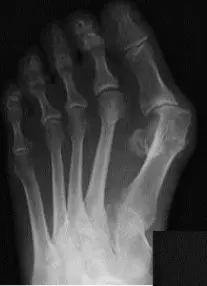

Radiology - Hallux Valgus

- XR views:

- AP standing:

- Lateral deviation of big toe

- Increased varus of 1st MT

- Subluxation of MT-Phal. joint